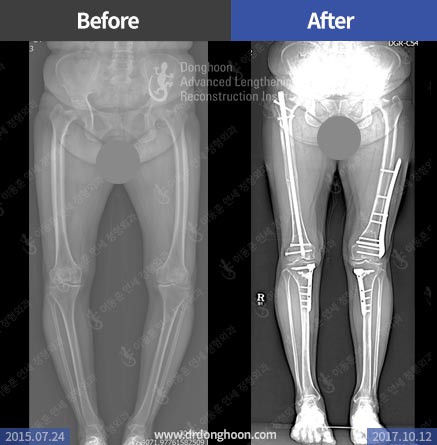

예시2. 허벅지뼈 및 종아리뼈의 복합변형으로 발생한 엑스다리 변형, 관절선 기울기 변형, 및 대퇴슬개 관절문제를 3차원적인 절골술을 통하여 치료함

일차원적이 아닌, 입체적인 교정 수술이 가능해야 합니다.

관절염 치료에서 제대로 된 절골술을 받을 수 있다면 새로운 다리를 선물 받는 것과 같습니다. 바람이 한쪽에서만 불지 않듯이, 관절염에서 휜다리의 방향도 꼭 한쪽 방향으로 생기라는 법은 없습니다.

관절은 입체적 구조이기 때문에 단순히 일차원적인 문제로만 인식하기 보다는 수술 전 상태와, 수술 후 영향을 입체적으로 분석하고 필요할 경우 입체적인 변형을 동시에 교정할 수 있는 의료진과 함께 하십시오.